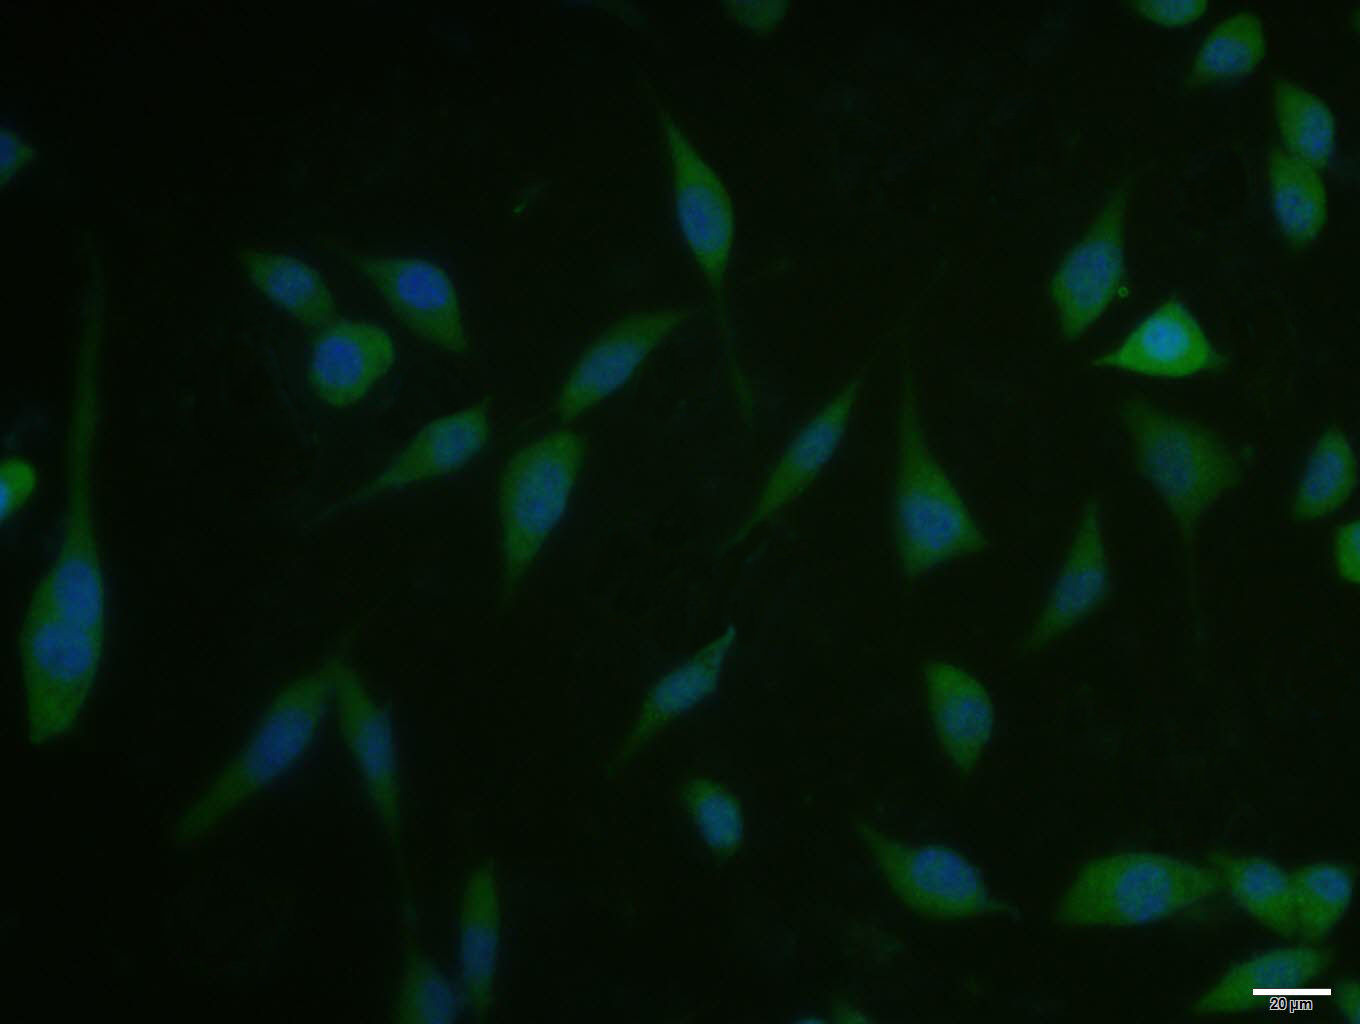

A431 cell; 4% Paraformaldehyde-fixed; Triton X-100 at room temperature for 20 min; Blocking buffer (normal goat serum, C-0005) at 37°C for 20 min; Antibody incubation with (Phospho-mTOR (Ser2481)) polyclonal Antibody, Unconjugated (bs-3495R) 1:100, 90 min